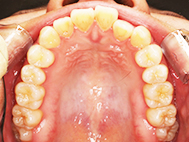

Before

| 症状 | 上下前歯叢生 |

| 治療内容 | 上顎部分裏側矯正 下顎は目立ちにくい透明な装置 |

| 治療期間 | 11ヶ月 |

左上の前歯内側に入っている下の前歯ガチャ歯

左上前歯が下の歯の内側に入っているのが気になるとの事で来院されました。目立たない矯正治療を希望しているとのこでした。 上顎の装置は、歯の裏側(リンガル装置)で下顎は表側で矯正治療を行いました。口を閉じた時、上の前歯が内側に入っている為に下の歯を前に押し出している状態でした。その為、上の歯を前に出すだけではその歯が下とのかみ合わせの関係で、前に飛び出すような治療となってしまいます。 今回の症例ではシュミレーションを見て頂き、下の歯も治療し、内側へ下げることによって上の歯も飛びだすことなく、キレイにおさまることを説明し、上下一緒に矯正することをお勧めさせて頂きました。